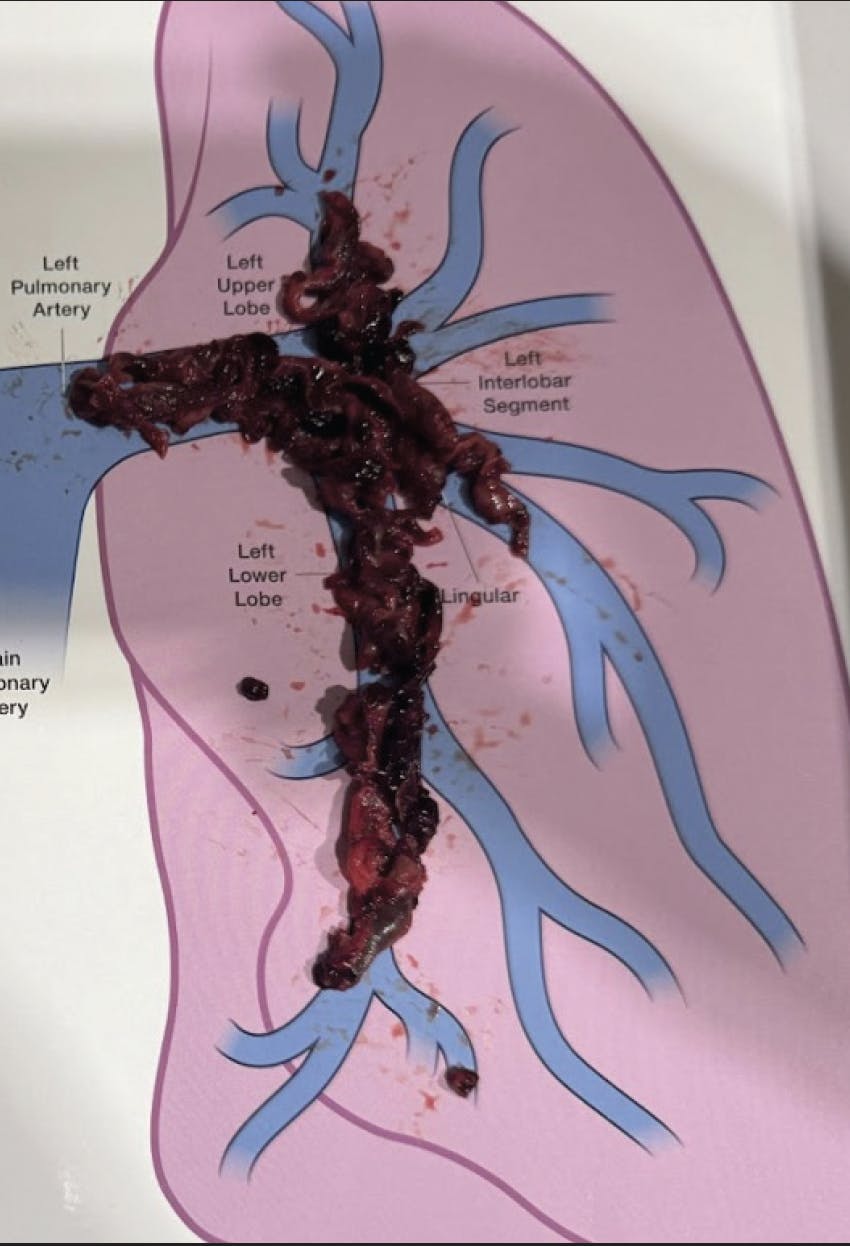

Pulmonary angiography demonstrated extensive thrombus in the left main PA and moderate distal thrombi in the right PA (Figure 3). The access site was preclosed with one Perclose ProGlide device (Abbott), and the sheath was upsized to a 16-F Gore DrySeal Flex introducer sheath (Gore & Associates) after serial dilation. A long J wire was advanced into the right PA, followed by introduction of the CAT16 aspiration catheter. After wire removal, CAVT was initiated, and multiple passes in the left PA extracted a significant amount of thrombus (Figure 4). Postthrombectomy angiography revealed marked reduction in clot burden (Figure 5). The total case time was 45 minutes, with a 3-minute device time using Lightning Flash 2.0. Final hemodynamics showed a PAP of 41/19 mm Hg (mean, 28 mm Hg). The 16-F sheath was removed, and hemostasis was achieved with one Perclose ProGlide.

Figure 4. Thrombus removed.